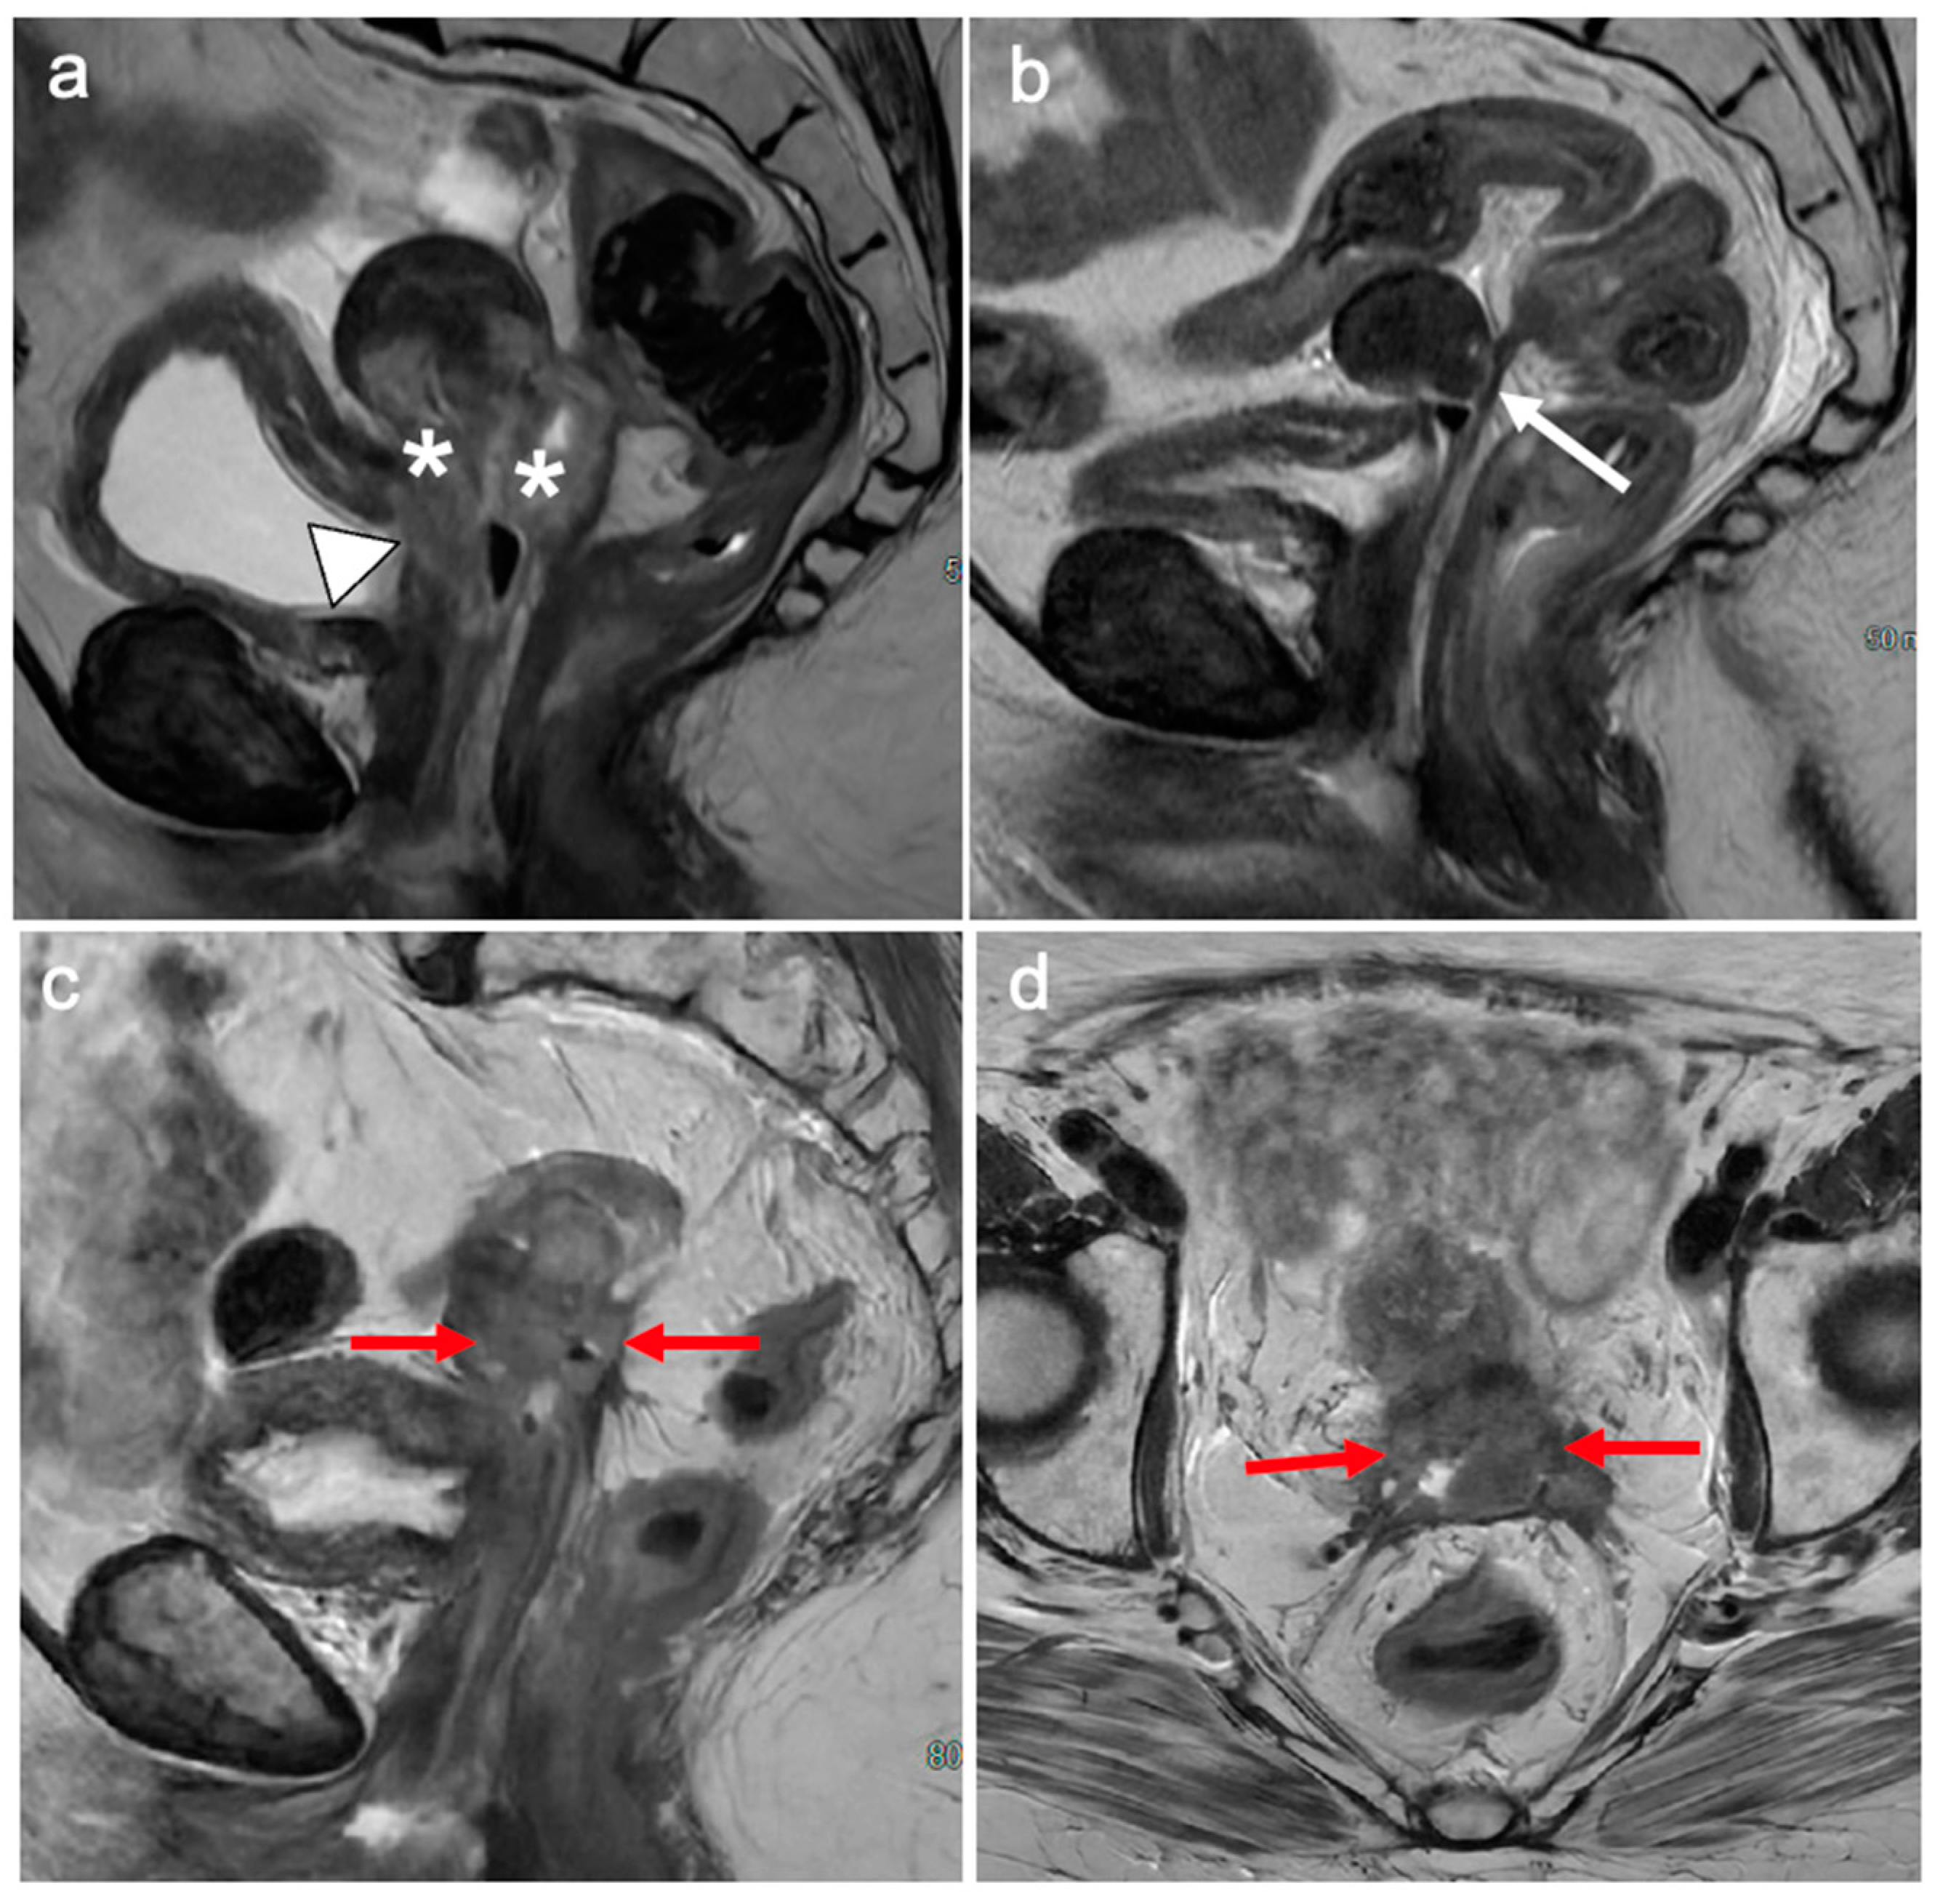

5. FIGO Stage II

9. Recurrent Cervical Cancer